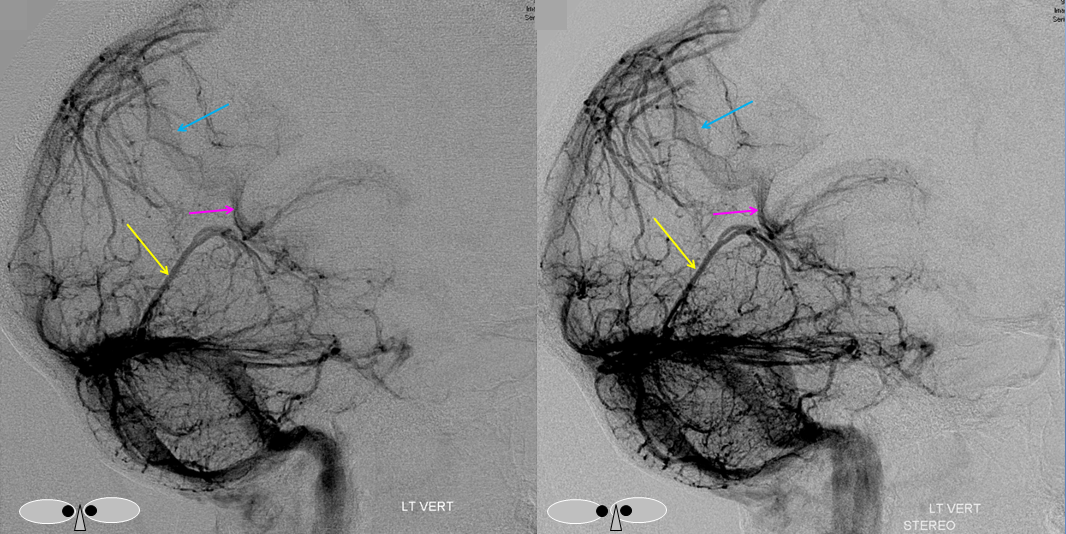

Following embolization, resection, recurrence (as frequently the case with childhood AVMs) and gamma-knife, things look good. Stereo, of course.

Following embolization, resection, recurrence (as frequently the case with childhood AVMs) and gamma-knife, things look good. Stereo, of course.